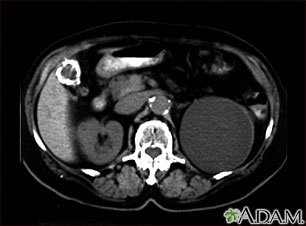

TC del abdomen superior mostrando un quiste del tamaño de un puño en el riñón izquierdo y cálculos biliares (el quiste del riñón se encontró por casualidad; no habían síntomas).